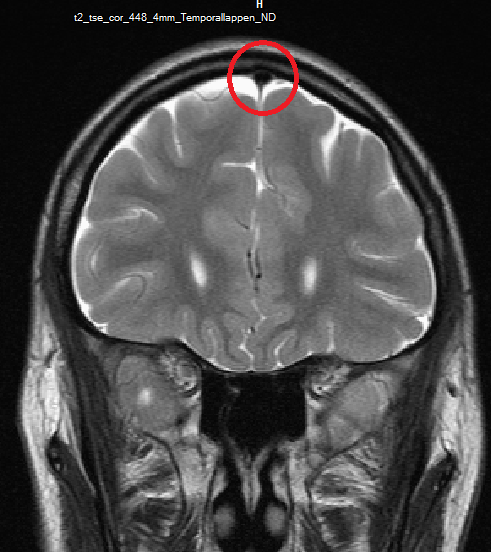

Mrt : Kuala Lumpur’s New MRT Map Alignment. ~ .: Property … / Support more model(qualcomm and … Retinoblastom (MRT/T2) – DocCheck

Retinoblastom (MRT/T2) – DocCheck MRT อิสรภาพ | hello darnon | Flickr

MRT อิสรภาพ | hello darnon | Flickr Beim MRT lagert sich giftiges Metall im Gehirn ab – WELT

Beim MRT lagert sich giftiges Metall im Gehirn ab – WELT Mrt 7 route map – Mrt 7 stations map (Republic of Singapore)

(16/26) MRT Schädel in Transversalebene, T₁‐gewichtet, FFE – DocCheck MRT Knie – DocCheck

MRT Übersichtsaufnahme – DocCheck MRT Schädel – DocCheck

MRT Schädel – DocCheck MRT Bild, könnte das ein Tumor sein? Kennt sich jemand damit aus? Könnte die helle Fläche ein …

MRT Bild, könnte das ein Tumor sein? Kennt sich jemand damit aus? Könnte die helle Fläche ein … Myokarditis (MRT) – DocCheck

MRT Schädel – DocCheck Sichere Prostatavorsorge mittels MRT-Untersuchung der Prostata

MRT Bild vom Kopf: Was ist das am rechten Ohr? (Nasennebenhöhlen) MRT Schädel, was ist das? (MRT Befund, Kontrastmittel)

MRT Schädel, was ist das? (MRT Befund, Kontrastmittel) MRT – Fleck im Knochen | Expertenrat Orthopädie | Lifeline | Das Gesundheitsportal

(11/26) MRT Schädel in Transversalebene, T₁‐gewichtet, FFE – DocCheck MS Herd MRT (1) – DocCheck

MS Herd MRT (1) – DocCheck Medizin – Gesundheit: Nierenzysten in MRI Abdomen medizinisches Bild

?wer kann helfen?ist in diesen MRT ein Tumor sichtbar? MRT abdomen – DocCheck

MRT Bild vom Kopf: Was ist das am rechten Ohr? (Nasennebenhöhlen) MRT Bilder vom 18. Februar 2002

MRT Kopf. Kleine Aufklärung? (Gesundheit, Medizin, Krankheit) Retinoblastom (MRT/T2) – DocCheck

(16/34) MRT Schädel in Sagittalebene, T₂‐gewichtet – DocCheck MRT Bilder-Hubbel-??? Hilfe (Kopf)

MRT Bilder-Hubbel-??? Hilfe (Kopf) รีวิว คอนโด Niche MONO อิสรภาพ เพียง 200 เมตร จาก MRT อิสรภาพ ใกล้ รพ.ศิริราช

MRT Schädel – DocCheck #MRT: Sungai Buloh – Kajang Line Phase 1 To Officially Start 16th December – Hype Malaysia

MRT 4 Schädel – DocCheck Taipei MRT Roadmap